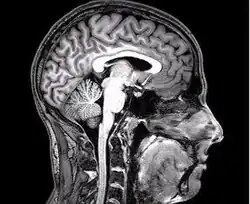

Neuropsychologia – dziedzina psychologiczna zajmująca się badaniem i opisywaniem związków zachodzących między układem nerwowym a procesami poznawczymi, głównie z perspektywy klinicznej, analizując konsekwencje uszkodzenia mózgu człowieka.

Jest to nauka z pogranicza medycyny i psychologii. W zakresie związków z naukami medycznymi jest bliska neurologii, psychiatrii oraz wyodrębniającej się od niedawna neuropsychiatrii. Ze strony nauk psychologicznych jest bliska psychometrii, psychologii klinicznej oraz biopsychologii (psychofizjologii, neurobiologii poznawczej, nazywanej też neuronauką poznawczą). Neuropsycholodzy pracują na uczelniach i w instytutach badawczych, zajmując się badaniami nad relacją między mózgiem a umysłem, jak i w ochronie zdrowia, zajmując się diagnostyką i rehabilitacją procesów poznawczych.